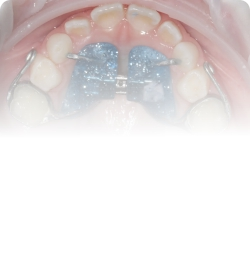

Несъемные аппараты для ортодонтического лечения

Главная задача аппаратов— не просто выровнять зубы, а создать правильные условия для роста челюстей и формирования прикуса.

Небные расширители (аппарат Марко Росса/Хааса). ТЗа счет постепенного раскрытия небного шва и раздвижения кости верхней челюсти в стороны, увеличивают пространство для зубов и улучшает форму зубного ряда.